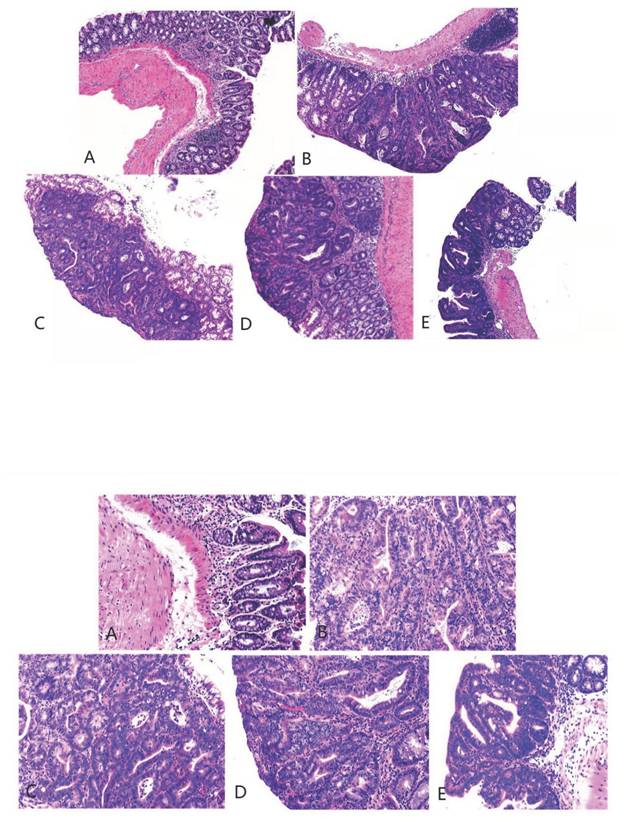

3.4. Hematoxylin and eosin staining and immunohistochemical staining

The pathological findings were tubular adenoma with low-grade intraepithelial neoplasia and carcinogenesis (Figure 5). The expression levels of ZO-1 and occludin in the colon tissues of mice in the four experimental groups decreased. In the model group, the expression of occludin and ZO-1 proteins significantly decreased. The expression levels of ZO-1 increased with the increase in the dose of metformin. However, no significant statistical difference was found between the medium- and high-dose groups. The results showed that the intestinal mucosal barrier of the CRC model mice was damaged to a different extent in each group. The damage in the model control group was the most extensive, followed by that in the low-, medium- and high-dose groups; however, these differences were not statistically significant (Figures 6 to 8).

Figure 5

Hematoxylin and eosin staining of colon cancer tissues obtained from the mice (magnification 40 as shown in [up] and 100 times [down]). A, B, C, D, and E represent the control and model, and low-, medium-, and high-dose groups treated with metformin, respectively.